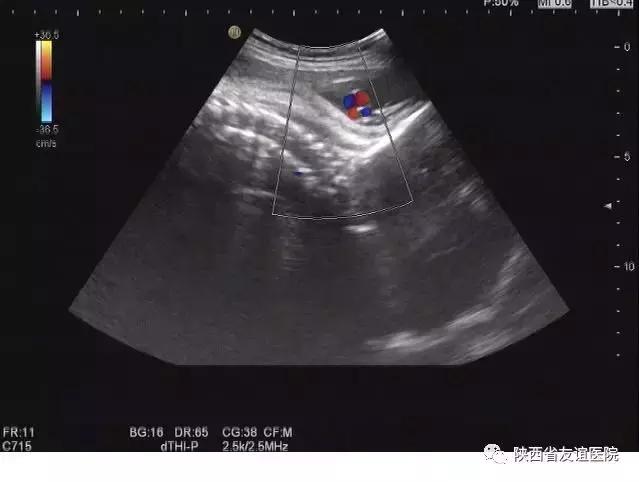

晚孕 B超图

五是超声检查可以准确估算孩子的体重

我在平时的胎儿检查,尤其是晚孕期胎儿检查中,经常会被孕妈妈问一个问题:“大夫,我的孩子有几斤重,能不能自己生呢?会不会太大?我听说超声可以估算体重,那我的孩子现在多重呢?”

首先,超声估算体重的方法是依据公式而算的,所用的数值主要是胎儿各个骨骼的径线,也就是说,B超测量的主要是胎儿的骨架,根据这些数值所估算的体重当然是不太准确的,因为每个宝宝的脂肪、肌肉和内脏的重量不尽相同。

其次,不同的超声仪器所自带的数据库也不一样,有的是欧美国家的数据库,有的是亚洲国家的数据库,同样测量出的径线,在不同的仪器上也会有不同的重量。

第三,每个超声医生的测量数值也会有差异。我们都知道,胎儿在妈妈肚子里存在各种各样的体位,这些都会影响超声医生的测量,就算是同一个医生,两次的测量结果也不一定相同,这就导致测量数据的偏差,那么在胎儿体重估算的时候就会不准确。

所以,B超估不准胎儿体重也是很正常的,如果想知道胎儿是否偏大不易生产时,最好还是请产科医生亲*摸自**一下最为妥当,一个经验丰富的产科医生会给孕妈妈提出合适的生产方案。